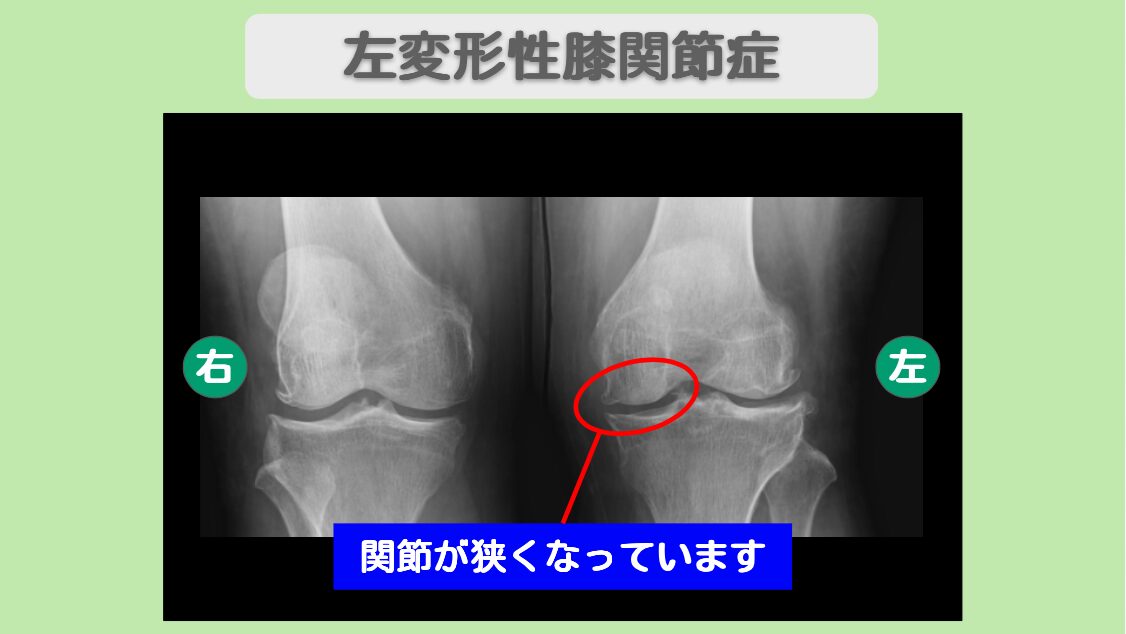

レントゲン所見

<治療内容>左股関節と左膝に1億個細胞を計3回投与+PRP

左股関節と左膝に1億個細胞を計3回投与しました。